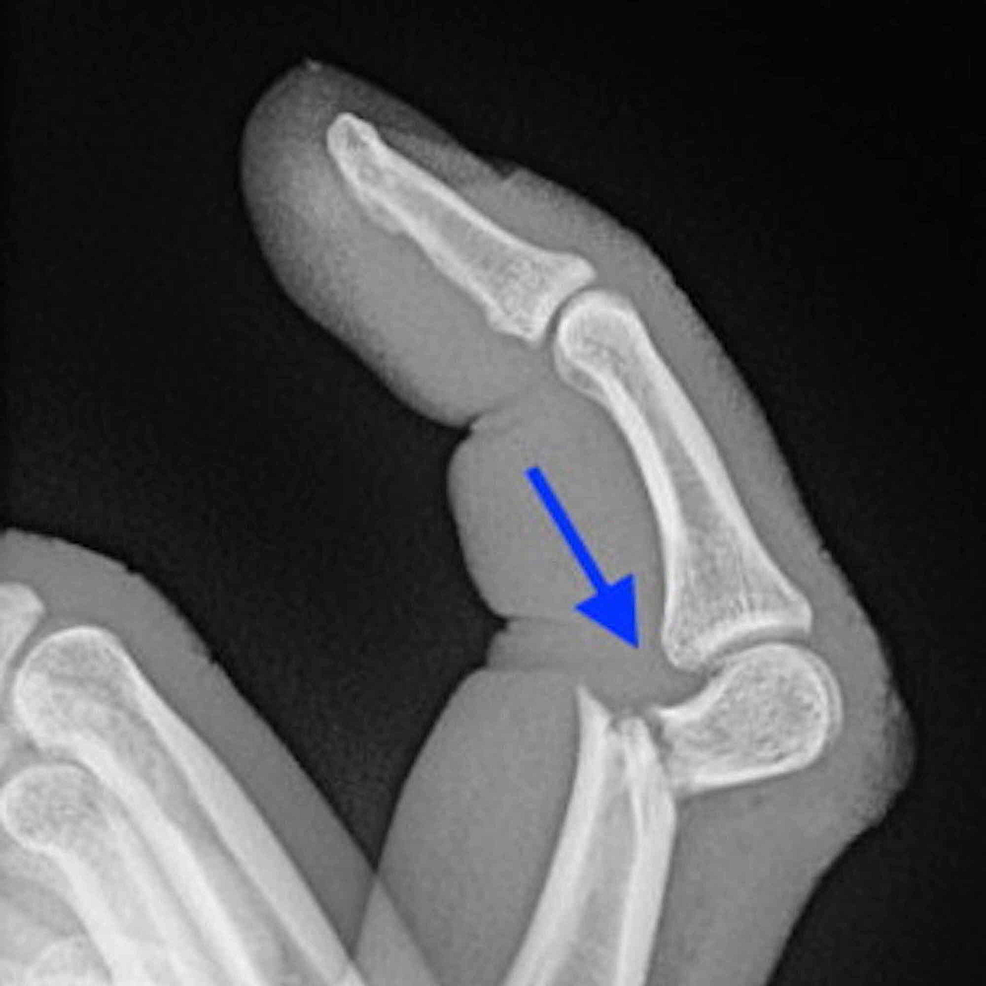

발가락 골절 증상·진단 포인트

- X-ray 2 방향 촬영이 1차 진단 표준

- 모호할 경우 CT/MRI 추가

- 수술(핀·스크루 고정)

- 변위 2 mm↑, 관절 선 불일치, 개방 골절일 때 선택